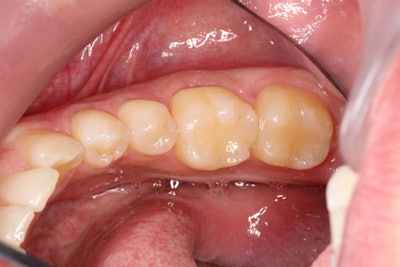

A 45-year-old patient presented to the dental practice complaining chiefly of a feeling of sharpness against his tongue. He was also experiencing slight sensitivity to sweets. An intraoral examination showed that an existing composite restoration on tooth #19 had fractured on the distal lingual aspect.

After the patient was anesthetized, isolation was obtained using the Isolite system (Zyris). The old restoration was removed, and the preparation was refined to eliminate any undercuts and decay, as well as ensure that it would draw. Following removal of the old restoration, a fine diamond (Red Stripe) was used to refine the preparation prior to taking the digital impression.